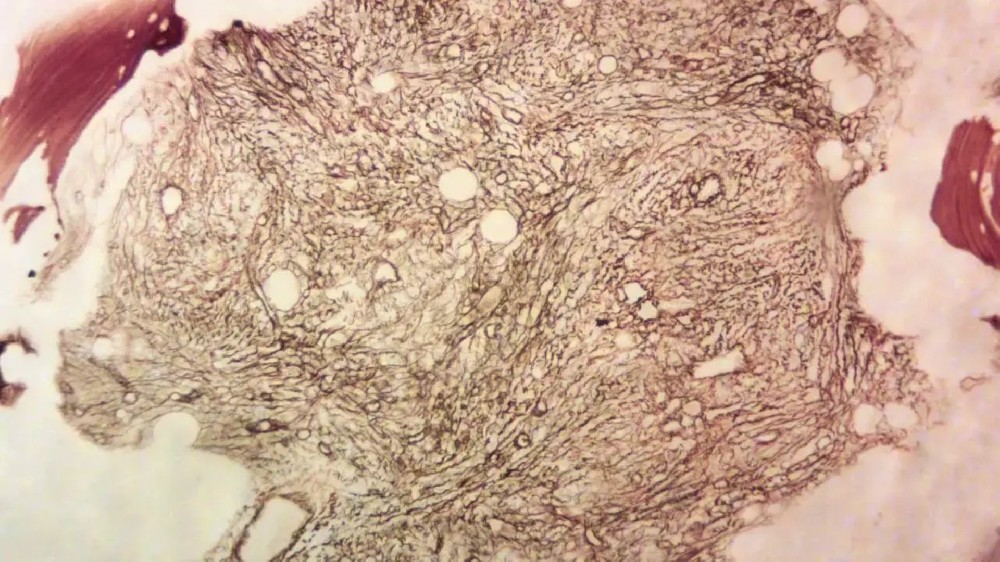

骨髓纖維化(原發性骨髓纖維化)是一種罕見但嚴重的慢性白血病,會破壞身體正常的血細胞製造。它會特別影響骨髓,造成進行性的疤痕(纖維化)。這種疤痕會抑制骨髓製造健康血細胞的能力,導致貧血、虛弱、疲勞,以及更容易受到感染。

骨髓活檢(確定診斷測試)